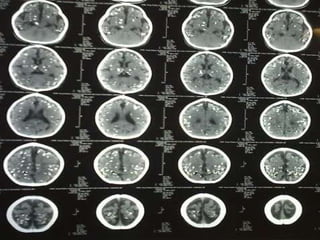

Múltiplas calcificações periventriculares associadas a hidrocefalia.  Há também calcificações na fossa posterior, situadas na substância branca cerebelar.

Múltiplas calcificações periventriculares associadas a hidrocefalia. Há também calcificações na fossa posterior, situadas na substância branca cerebelar.   Caso clínico do Dr. Paulo R. Margotto / HFA/EMFA

USG e TC Crânio A incidência de anomalias ultra-sonografias varia de 18,1% a 36,4%, estando associada à idade gestacional da infecção fetal As alterações observadas com maior freqüência são dilatação ventricular e calcificações intracranianas  Berrebi A, Bessières MH, Cohen-Khalas Y, et al. Diagnostic anténatal de la toxoplasmose. A propos de 176 cas. J Gynecol Obstet Biol Reprod (Paris) 1993; 22:261-8  Hohlfield P, MacAleese J, Capella-Pavlovski M, et al. Fetal toxoplasmosis: ultrasonographic signs. Ultrasound Obstet Gynecol 1991; 1:241-4.